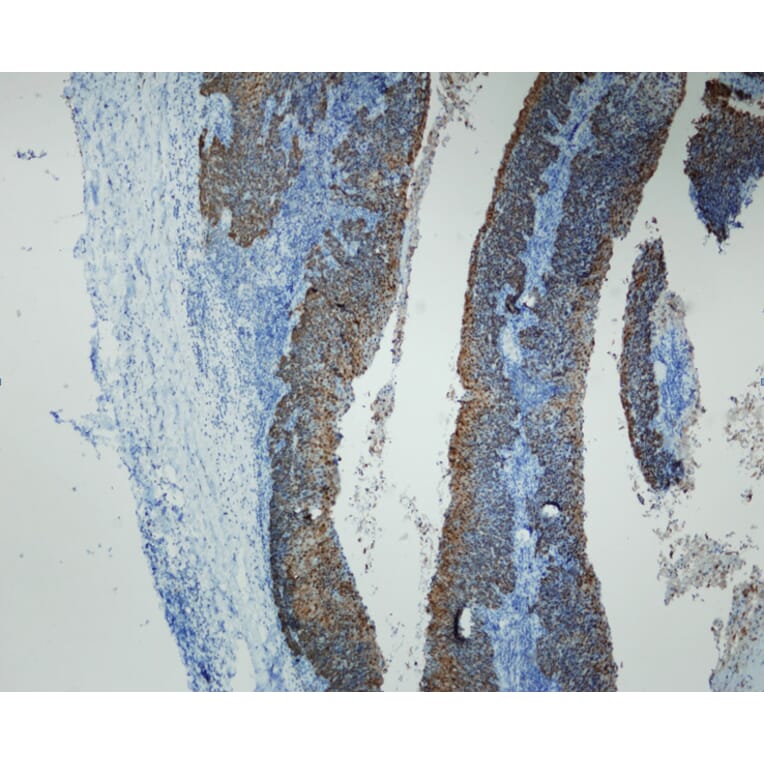

High grade squamous intraepithelial lesion of the uterine cervix (in contrast with normal endocervical glands) stained with Anti-p16 Antibody (A8237). Shows strong and specific positive immunostaining of dysplastic and neoplastic epithelium, with no reactivity in normal epithelial and stromal structures. Formalin fixed, paraffin embedded human tissues (4µm sections) stained.